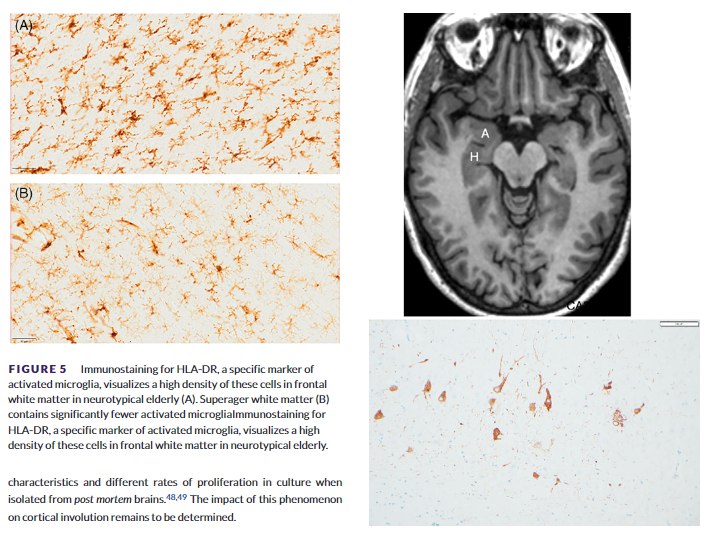

“超级大脑”的秘密首先在于其对疾病的强大抵抗力。研究显示,与普通同龄人相比,超级老人的大脑中,阿尔茨海默病的典型病理标志——神经纤维缠结——要少得多 。同时,他们大脑内部的炎症水平更低,表现为更少的炎性小胶质细胞,这为神经元提供了一个更健康的运作环境 。此外,其负责记忆和注意力的胆碱能神经系统功能也保存得更完好 。